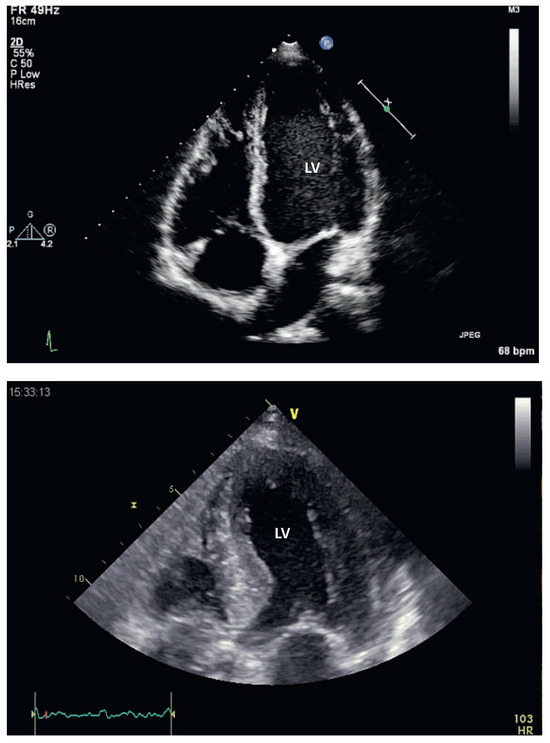

Interesting Images

Lost in Space - Left Lateral Cardiac Displacement Due to an Unusual Cause

by Niels Holm, Esther Bächli and Tobias Hoefflinghaus

Cardiovasc. Med. 2014, 17(2), 55; https://doi.org/10.4414/cvm.2014.00223 - 19 Feb 2014

Viewed by 110

Abstract

We present a case of an incidental finding of congenital absent pericardium (CAP) [...] Full article

Show Figures

Figure 1